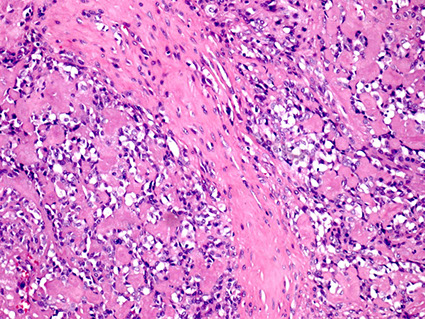

Myoepithelial carcinoma

- aka malignant myoepithelioma

tumor made almost entirely of myoepithelial cells, mostly in parotids, M=F

- grossly uncircumscribed

Micro: multinodular c infiltration into adjacent tissues

- nodules are solid and in sheets c lots of mcous and sometimes central necrosis, can have variable histology

- nuclei can range from relative calm looking to ramped up, and can have few to lots of mits

- 1/2 have perineural invasion

- no true glands or lumina seen

IHC: (+) S100 (all have some degree of staining), myoepithelial markers (muscle-specific actin, GFAP, CD10, calponin, smooth muscle myosin heavy chain), CK, glycogen, Alcian blue (in myxoid matrix), p63 (3/5), smooth muscle actin (3/5),

- neg: mucicarmine (if doesn't have glands)

Px: 1/3 of pts die of the dz, 1/3 get recurrences and 1/3 dz free